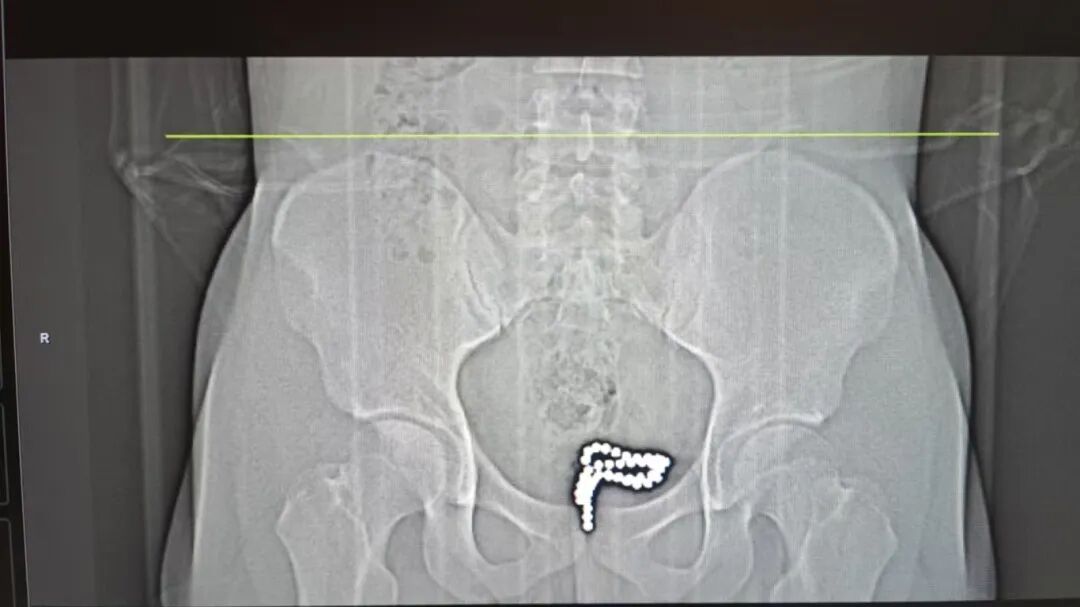

患者今年18岁,因自述2小时前自行向尿道内放入多颗磁力珠,随后无法取出,伴有明显阴茎胀痛感,紧急来我院就诊。急诊科医生详细询问病史后,尝试取出部分异物,随即复查盆腔CT提示:膀胱内可见高密度异物影,金属伪影明显,提示仍有大量磁力珠残留于膀胱。

面对这些技术难点,手术团队沉着应对,在麻醉科医师的配合下,采用膀胱尿道电切镜系统进行探查。术中见膀胱三角区黏膜轻度充血,双侧输尿管开口清晰,膀胱内可见散在分布的多颗彩色磁力珠,大小约2mm×2mm,经清点共计48颗。